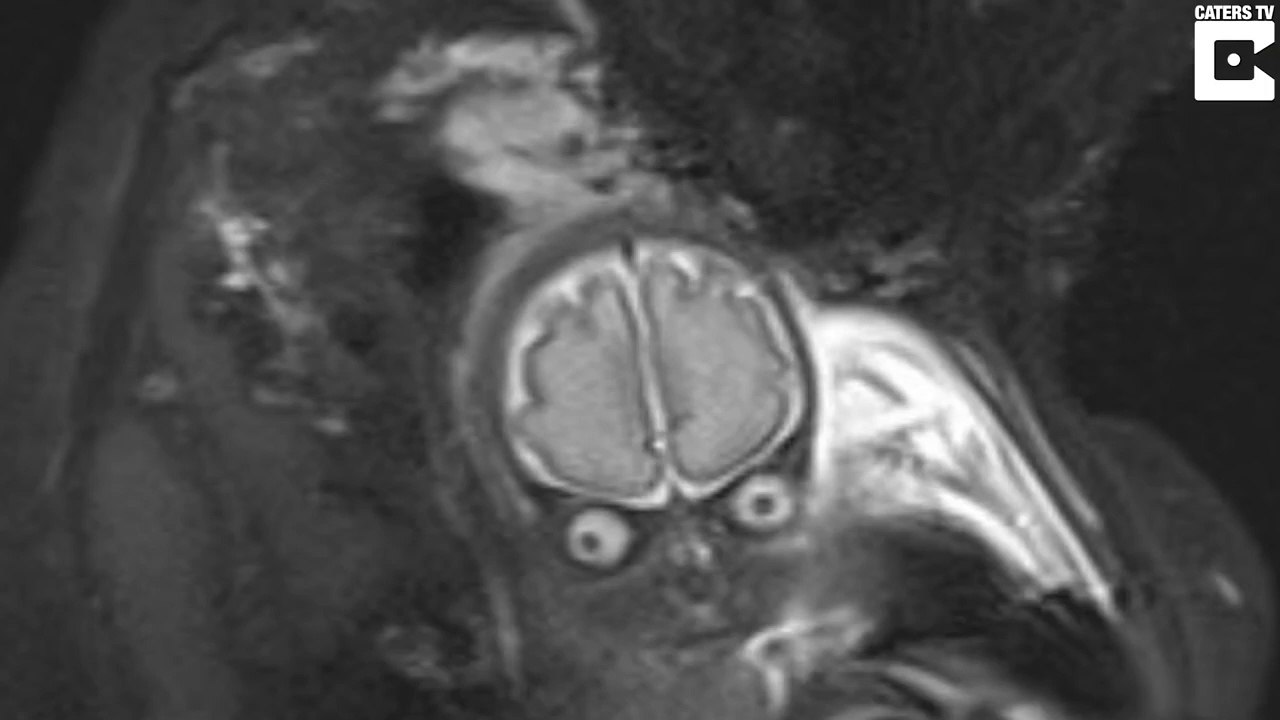

Elle fait faire une IRM du cerveau à son bébé et va avoir la peur de sa vie 0:49

Elle fait faire une IRM du cerveau à son bébé et va avo...

Mister Buzz 94 views